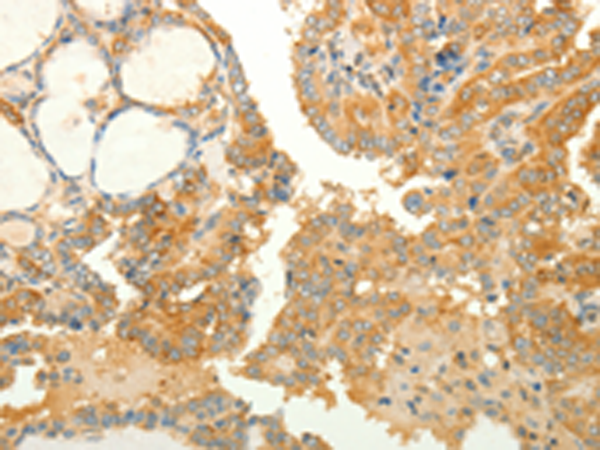

分类: 科研抗体货号: P10658别名: CD246, NBLST3应用: IHC反应种属: Human, Mouse

-